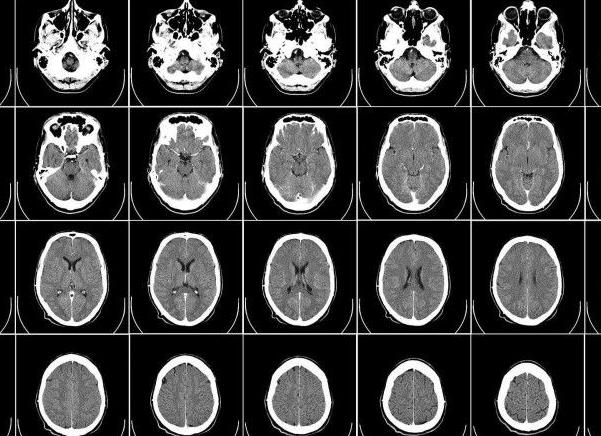

Снимок МРТ головного мозга

При этом томография способна выявить причины этих признаков. Как правило, они связаны с нарушением мозгового кровообращения, воспалительными процессами в структурах мозга, черепно-мозговыми травмами или опухолями. Диагностируются кисты, гематомы, области, пораженные ишемическими процессами. Этот метод показан при диагностике эпилепсии.

МРТ головного мозга – это очень важное исследование, которое проводится в различных режимах (их разработано достаточно много). Также проводят еще трактографию, которая позволяет исследовать белое вещество мозга. Таким образом, диагностировать можно поражения мозга, что имеют токсический, механический или радиационный характер. При определении патологий головного мозга, которые провоцируют проявление определенных симптомов дополнительно исследуются глазные яблоки, шейный отдел и нервы.